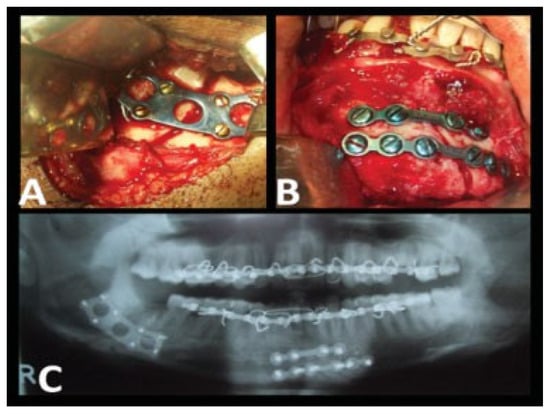

| Case no. | Fractured site | Surgical approach | Special apparatus used |

| 1 | Rt. parasymphysis and Lt. angle | Extraoral | |

| 2 | Lt. angle | Extraoral | |

| 3 | Rt. parasymphysis and Lt. angle | Extraoral | |

| 4 | Lt. angle | Extraoral | |

| 5 | Lt. angle | Extraoral | |

| 6 | Lt. body and Rt. angle | Extraoral | |

| 7 | Lt. angle | Transbuccal | Transbuccal kit |

| 8 | Lt. parasymphysis and Rt. angle | Extraoral | |

| 9 | Lt. parasymphysis and Rt. angle | Extraoral | |

| 10 | Rt. angle | Extraoral | |

| 11 | Rt. angle | Extraoral | |

| 12 | Lt. angle | Transbuccal | Transbuccal kit |

| 13 | Rt. parasymphysis and Lt. angle | Extraoral | |

| 14 | B/l angle | Extraoral | |

| 15 | Lt. parasymphysis and Rt. angle | Extraoral | |

| 16 | Rt. parasymphysis and Lt. angle | Extraoral | |

| 17 | Lt. angle | Extraoral | |

| 18 | Lt. angle | Extraoral | |

| 19 | Rt. angle | Extraoral | |

| 20 | Lt. parasymphysis and Rt. angle | Extraoral |